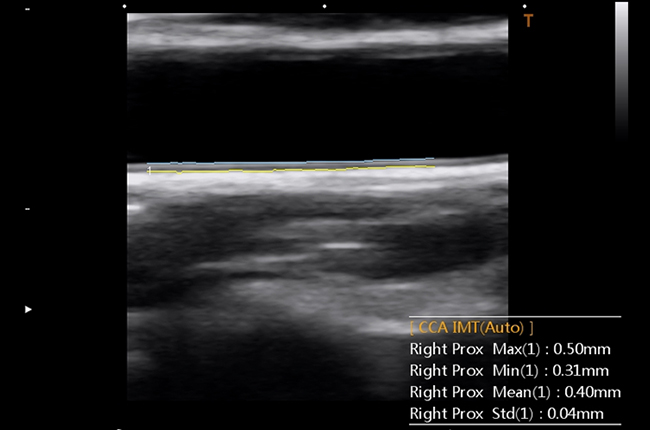

Сонна артерія